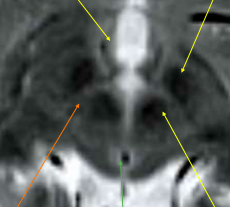

Label A-C

A: **Anterior commissure** B: **Amygdala** C: **Hippocampal**

What is 13? Hypothalamus Fornix Amygdala Hippocampus Thalamus

What is 5? Hypothalamus Fornix **Amygdala** Hippocampus Thalamus